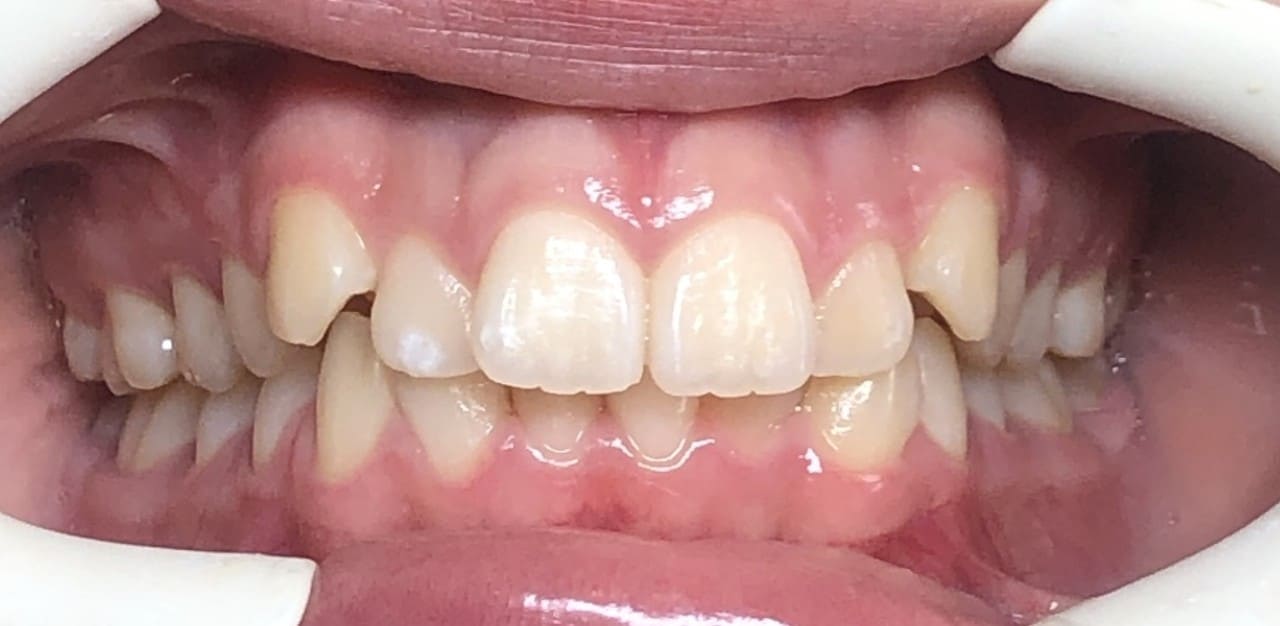

Initial

Final